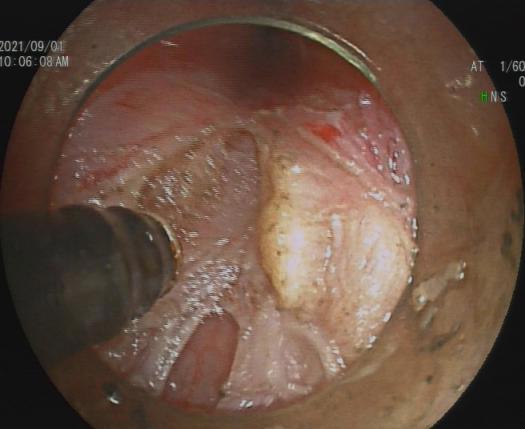

直肠巨大绒毛状腺瘤 内镜下粘膜剥离过程

粘膜剥离术后创面 剥离的巨大腺瘤

内镜下粘膜剥离术(ESD),具有超级微创、安全性高、住院时间短及费用低等优势。